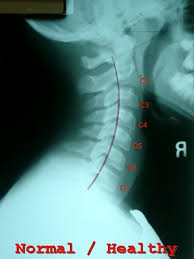

Healthy?C Spine X Ray - How To Read C Spine X Ray International Emergency Medicine Education Project - It's commonly done after someone has been in an automobile or other accident.

This procedure may be used to diagnose back or neck pain, fractures or broken bones, arthritis, degeneration of the disks, tumors, or other problems. Enter search terms and tap the search button. They show pictures of your internal tissues, bones, and organs. Please understand that our phone lines must be clear for urg. Here's what to expect with this painless procedure and why your dentist may recommend it.